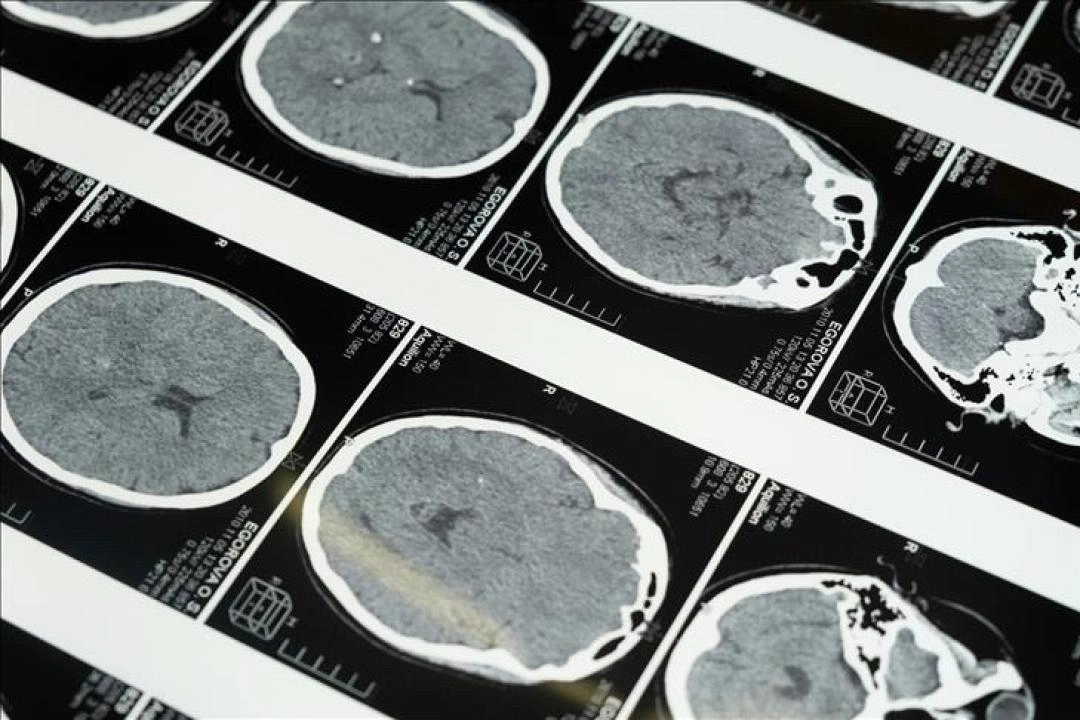

İstanbul'da düzenlenen 1. Dünya Girişimsel Nöroloji ve Nöroşirürji Kongresi'nin (WINNC 2025) düzenleme komitesinde yer alan Eskişehir Osmangazi Üniversitesi Tıp Fakültesi Nöroloji Ana Bilim Dalı Öğretim Üyesi ve İnme Merkezi Sorumlusu Prof. Dr. Atilla Özcan Özdemir, inmenin beyin damarlarının tıkanması (iskemik) ve beyin kanaması şeklinde gelişen iki türünün olduğunu söyledi.

"Özellikle pıhtıyla tıkanan beyin damarının açılmasıyla ilgili stratejiler gelişti. İnmede erken dönemde yapılan damar açma tedavileri konusunda ülke olarak iyi durumdayız. İnme tedavisinde pıhtıyla tıkalı beyin damarının anjiyo yoluyla açılması mümkün. Böylelikle hastanın 3 ay sonra, 1 yıl sonra kendi işini yapabilecek hale getirilmesi sağlanabiliyor. İnme merkezlerinde uygulanabilen bu işlemi ilk 24 saat içerisinde belirli hasta gruplarına yapabiliyoruz. İlk 24 saat çok kritik, bu müdahaleler de sadece inme merkezlerinde yapılabiliyor."